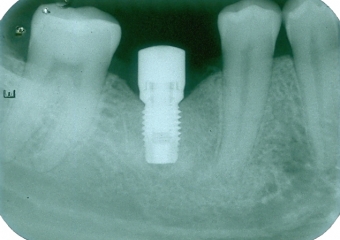

Raio X inicial